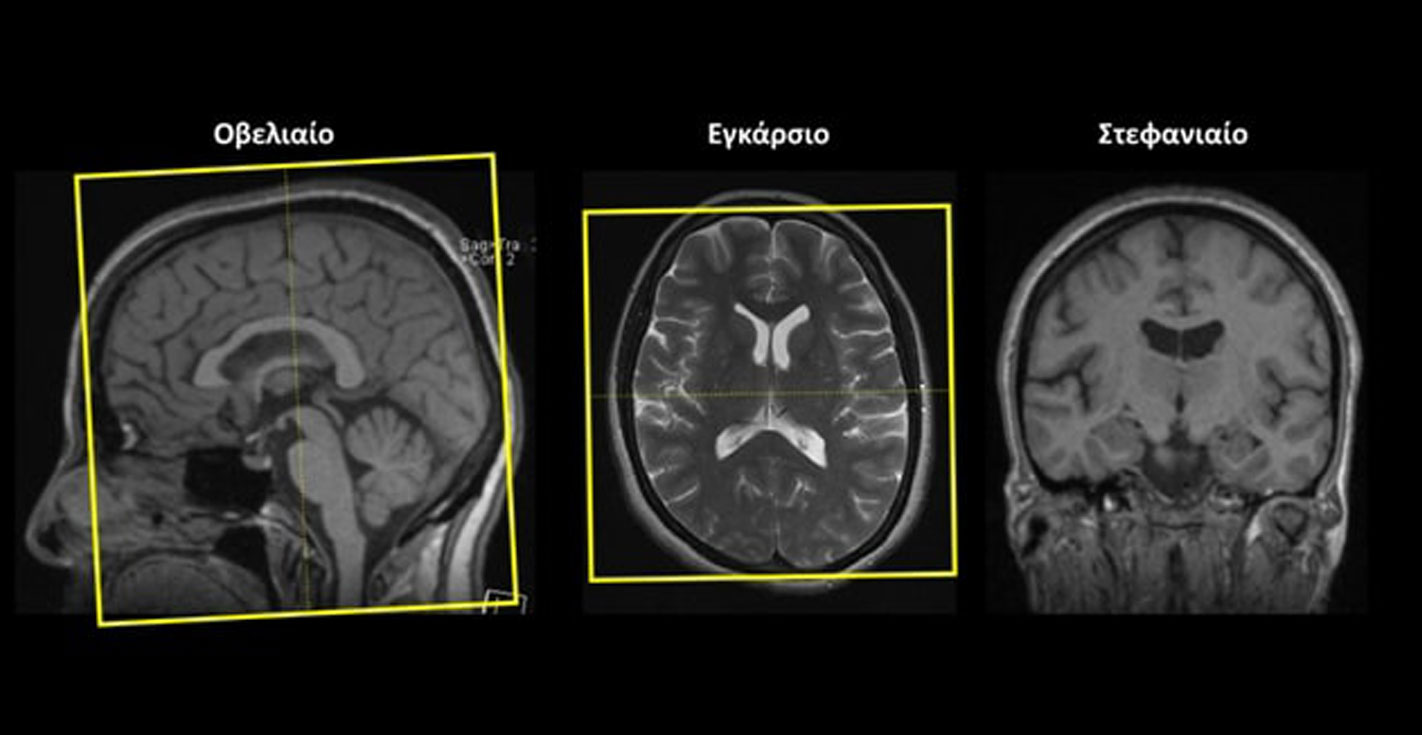

Εγκάρσιο (Axial/Transversal): οι εγκάρσιες τομές σχεδιάζονται παράλληλα με το πρόσθιο (γόνυ) και το οπίσθιο (σπληνίο) κέρας του μεσολοβίουστο οβελιαίο επίπεδο και κάθετα στη μέση γραμμή του εγκεφάλου στο στεφανιαίο επίπεδο. Οι τομές πρέπει να περιλαμβάνουν ολόκληρο τον εγκέφαλο έως και την παρεγκεφαλίδα (κάτω).

Οβελιαίο (Sagittal):οι οβελιαίες τομές σχεδιάζονται παράλληλα με τη μέση γραμμή του εγκεφάλου τόσο στο στεφανιαίο όσο και στο εγκάρσιο επίπεδο. Οι τομές πρέπει να περιλαμβάνουν ολόκληρο τον εγκέφαλο.

Στεφανιαίο (Coronal): οι στεφανιαίες τομές σχεδιάζονται κάθετα με τη νοητή γραμμή που ενώνει το πρόσθιο (γόνυ) και το οπίσθιο (σπληνίο) κέρας του μεσολοβίου στο οβελιαίο επίπεδο και κάθετα στη μέση γραμμή του εγκεφάλου στο εγκάρσιο επίπεδο. Οι τομές πρέπει να περιλαμβάνουν ολόκληρο τον εγκέφαλο.